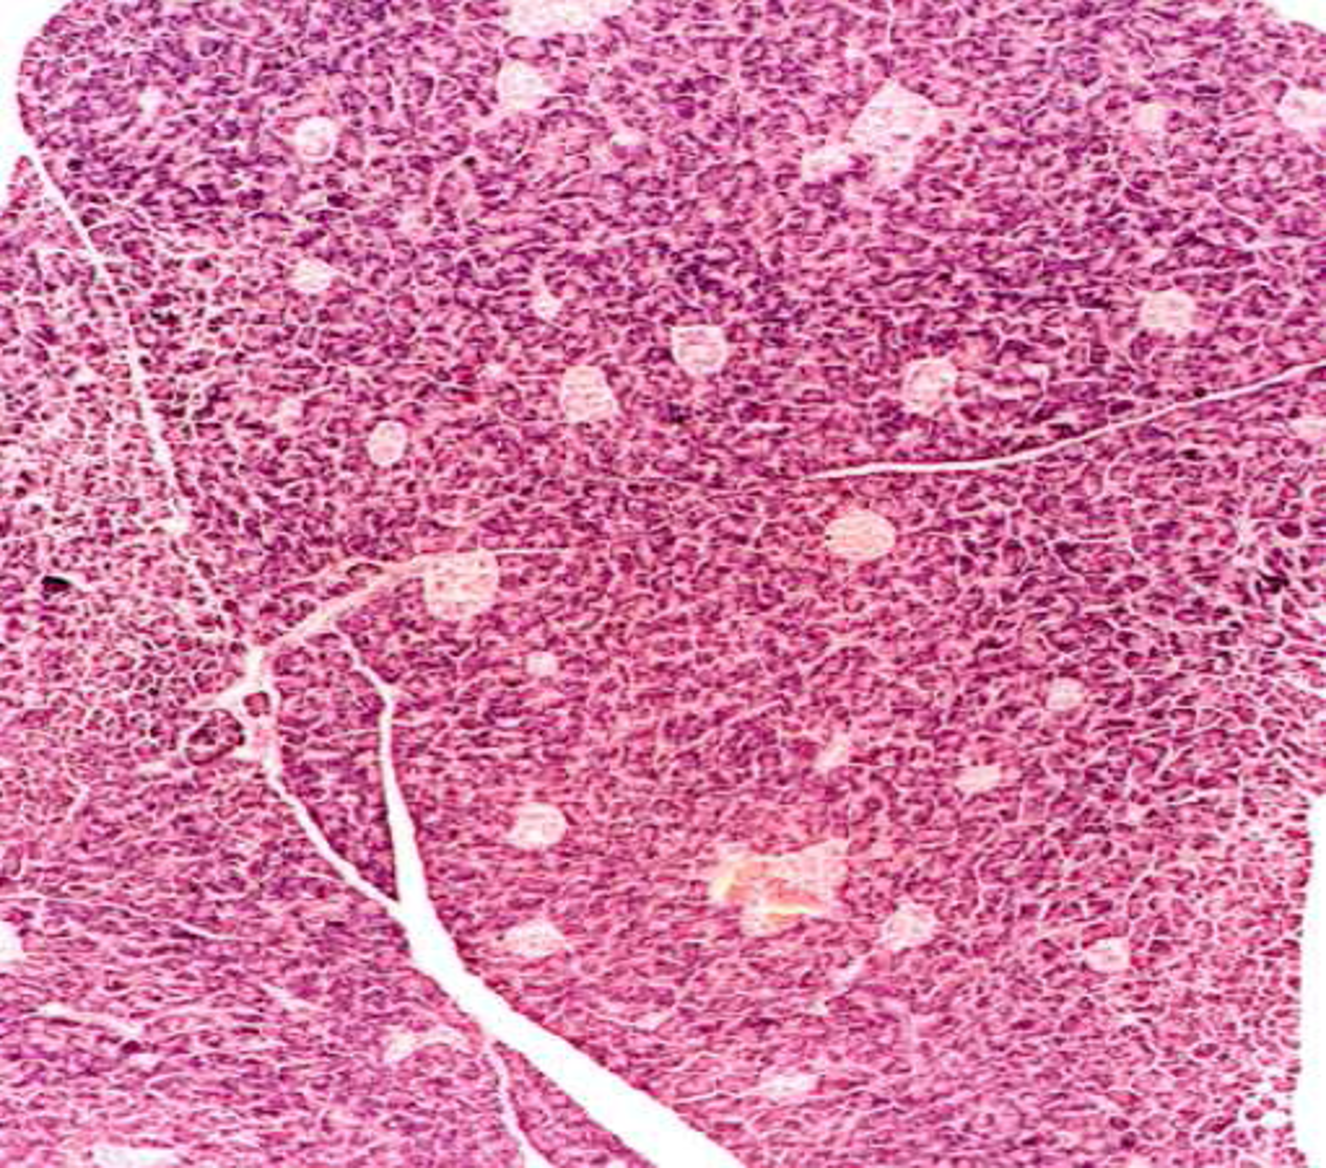

32

pancreas

what is this and what are the labels indicating

liver